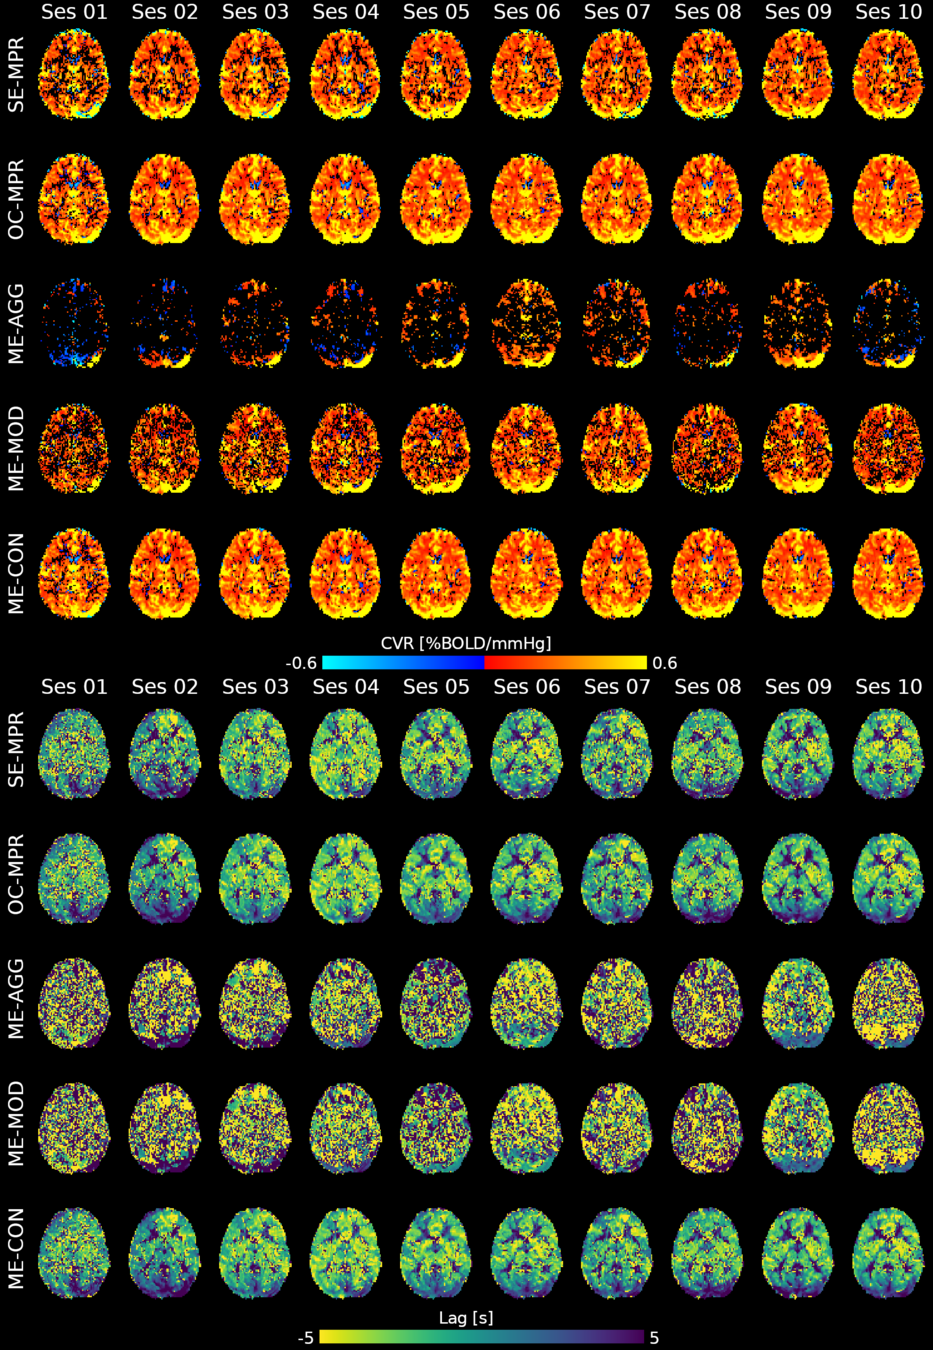

Methods: ME-ICA based denoise

What is the best way to denoise BH data after ICA?

being too aggressive might remove the signal of interest,

but being too conservative might keep too much noise in the model.

- Aggressive model: nuisance regression using only noise ICA-components (ME-AGG): $$ Y_{OC} = P_{ET}CO_2{hrf} + Mot + Poly + [IC_{rej} \perp (Mot,Poly) ] + n $$

- Moderate model: noise components are orthogonalised w.r.t. the CO2 trace (ME-MOD): $$ Y_{OC} = P_{ET}CO_2{hrf} + Mot + Poly + [IC_{rej} \perp (P_{ET}CO_2{hrf},Mot,Poly) ] + n $$

- Conservative model: noise components are orthogonalised w.r.t. the CO2 trace and the other components (ME-CON): $$ Y_{OC} = P_{ET}CO_2{hrf} + Mot + Poly + [IC_{rej} \perp (P_{ET}CO_2{hrf},IC_{acc},Mot,Poly) ] + n $$

- Optimal combination only (OC-MPR): $$ Y_{OC} = P_{ET}CO_2{hrf} + Mot + Poly + n $$

- Single echo only (second echo used as proxy, SE-MPR): $$ Y_{SE} = P_{ET}CO_2{hrf} + Mot + Poly + n $$

We set up a simultaneous estimation and denoise step, considering motion parameters,

their derivative, Legendre polynomials to the fourth order, and:

- Aggressive model: nuisance regression using only noise ICA-components (ME-AGG): $$ Y_{OC} = P_{ET}CO_2{hrf} + Mot + Poly + [IC_{rej} \perp (Mot,Poly) ] + n $$

- Moderate model: noise components are orthogonalised w.r.t. the CO2 trace (ME-MOD): $$ Y_{OC} = P_{ET}CO_2{hrf} + Mot + Poly + [IC_{rej} \perp (P_{ET}CO_2{hrf},Mot,Poly) ] + n $$

- Conservative model: noise components are orthogonalised w.r.t. the CO2 trace and the other components (ME-CON): $$ Y_{OC} = P_{ET}CO_2{hrf} + Mot + Poly + [IC_{rej} \perp (P_{ET}CO_2{hrf},IC_{acc},Mot,Poly) ] + n $$

- Optimal combination only (OC-MPR): $$ Y_{OC} = P_{ET}CO_2{hrf} + Mot + Poly + n $$

- Single echo only (second echo used as proxy, SE-MPR): $$ Y_{SE} = P_{ET}CO_2{hrf} + Mot + Poly + n $$

Methods: ME-ICA based denoise

Results: CVR amplitude maps

Moia et al. 2021 (NeuroImage)

Results: lag maps

Moia et al. 2021 (NeuroImage)

Results: lag maps

Moia et al. 2021 (NeuroImage)